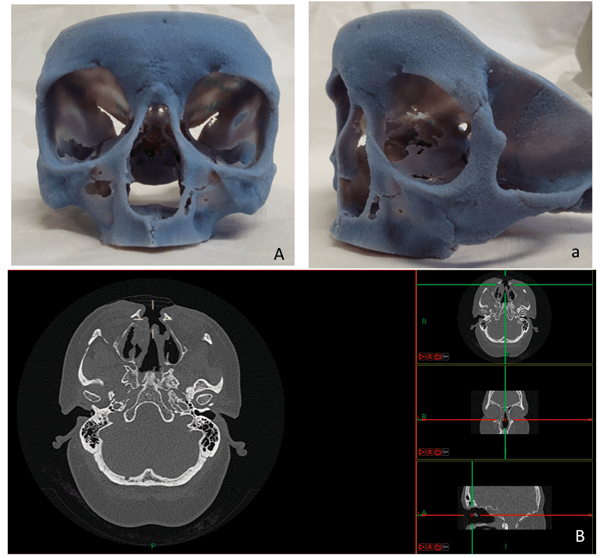

Figure 3. The 3D model of a patient following total rhinectomy and adjuvant radiotherapy prior the implantation of the abutments for the prosthesis (A/a) and the CT in three planes (B); the 3D print is utilised to find the areas with the thicker bone to safely accommodate the implant.

The 3D-prints (see Figures 1-3) are based on a high-resolution computed tomography (HRCT) scan of the temporal bone and the skull with a thickness of 0.5-0.6 mm (scans performed in various scanners in our department). The patient’s HRCT scan is exported into a 3D software package (Mimics, Materialise, Leuven, Belgium) to convert in to a digital imaging and communications in medicine (DICOM) file to which can be manipulated to reduce and target certain areas. The import of the DICOM file can easily and quickly create accurate 3D models. The software package allows the operator to anatomically analyse and virtually simulate surgery on screen. The final process involved exporting the 3D analysis and the printing of the 3D model. The stereolithographic file was exported to the 3D printer and the printing of model was finalised. We used the printer OBJET 30 (OBJECT 30, Stratasys, MN, United States) and rigid opaque photopolymers (Vero blue) as the printing material for our models; a material that allows detailed printing in blue colour (see Figures 1-3). The time needed for each 3D-model varied between 16 and 22 hours with an approximate cost of £340-£380 for every detailed model for an in-house production. Most of the time is associated with the actual printing, which is usually done overnight.

In cases of implantation of a prosthetic nose, the 3D print is used to identify the area with the thickest bone, where the implants can safely be placed. Considering that in cases of total rhinectomy due to malignancy, adjuvant radiotherapy will be used, resulting in poor bone quality, the identification of the most suitable areas for better placement seems extremely valuable. The software package can allow for measuring bone density and enabling surgical colleagues to correctly navigate and place implants in the correct vector.